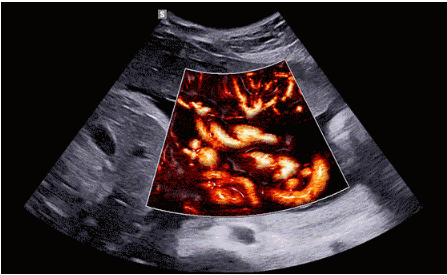

近日三星醫(yī)療推出了一款全新的母嬰超聲系統(tǒng)——Hera i 10。該款產(chǎn)品除了成像能力本身,人性化的座椅設(shè)計(jì),探頭擺放位置等也是亮點(diǎn)之一。

Hera i 10繼承并升級(jí)了全球首款5D超聲“三星麥迪遜WS80A”的“晶體結(jié)構(gòu)”成像理念,即將CrystalBeam?波束形成技術(shù)、CrystalLive?超聲成像引擎、S-Vue Transducer?視覺傳感器集于一身,提供更清晰的圖像。

CrystalLive?是三星最新的超聲成像引擎,同時(shí)增強(qiáng)了2D圖像處理能力、3D渲染能力和彩色信號(hào)處理能力,能夠在復(fù)雜情況下提供出色的圖像性能,具備檢測外周血管、微循環(huán)血流的能力。

3D/4D成像方面,Hera i 10通過結(jié)合先進(jìn)的圖像渲染技術(shù),著重加強(qiáng)了邊緣和小結(jié)構(gòu)的可視化能力。